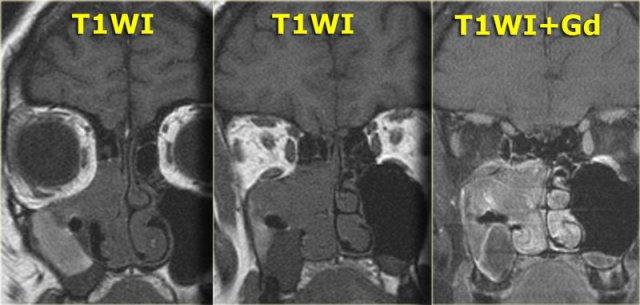

Khi muốn phân biệt dịch tiết cô đặc với khối u tân sinh, điều quan trọng là phải có hình ảnh trước và sau tiêm thuốc tương phản từ.

Nếu chỉ nhìn vào hình sau tiêm thuốc ở bên phải, bạn có thể bị nhầm lẫn khi cho rằng có sự ngấm thuốc đồng nhất của khối trong hốc mũi (dấu hoa thị) cũng như trong xoang sàng và xoang hàm bên phải.

Tuy nhiên, khi nhìn vào hình trước tiêm thuốc, bạn sẽ nhận thấy rằng nội dung trong xoang sàng và xoang hàm tăng tín hiệu so với khối trong hốc mũi (vùng khe mũi giữa), vì các xoang này chứa đầy dịch tiết cô đặc.

Khối ngấm thuốc đồng nhất này phải được coi là khối u cho đến khi được chứng minh ngược lại.

Các dấu hiệu hình ảnh không đặc hiệu và chẩn đoán phân biệt bao gồm polyp hoặc ung thư biểu mô.

Sinh thiết xác nhận là u nhú đảo ngược.

Hình T1W trước tiêm thuốc cho thấy một vùng tăng tín hiệu trong xoang hàm, tương ứng với chất dịch giàu protein.

Phía trong của vùng đó là một vùng giảm tín hiệu tương tự tín hiệu của nhãn cầu (có thể là dạng nang).

Phần lớn mô mềm trong xoang hàm phải tương đối giảm tín hiệu trên hình T1W trước tiêm thuốc,

nhưng ngấm thuốc đồng nhất, gợi ý khối u.

Hình T2W bên trái xác nhận thành phần dạng nang (mũi tên vàng).

Hình CT mặt phẳng coronal minh họa rõ nét hình ảnh tái cấu trúc xương và giãn nở (đầu mũi tên).

Kết quả giải phẫu bệnh xác nhận là u nhú đảo ngược.